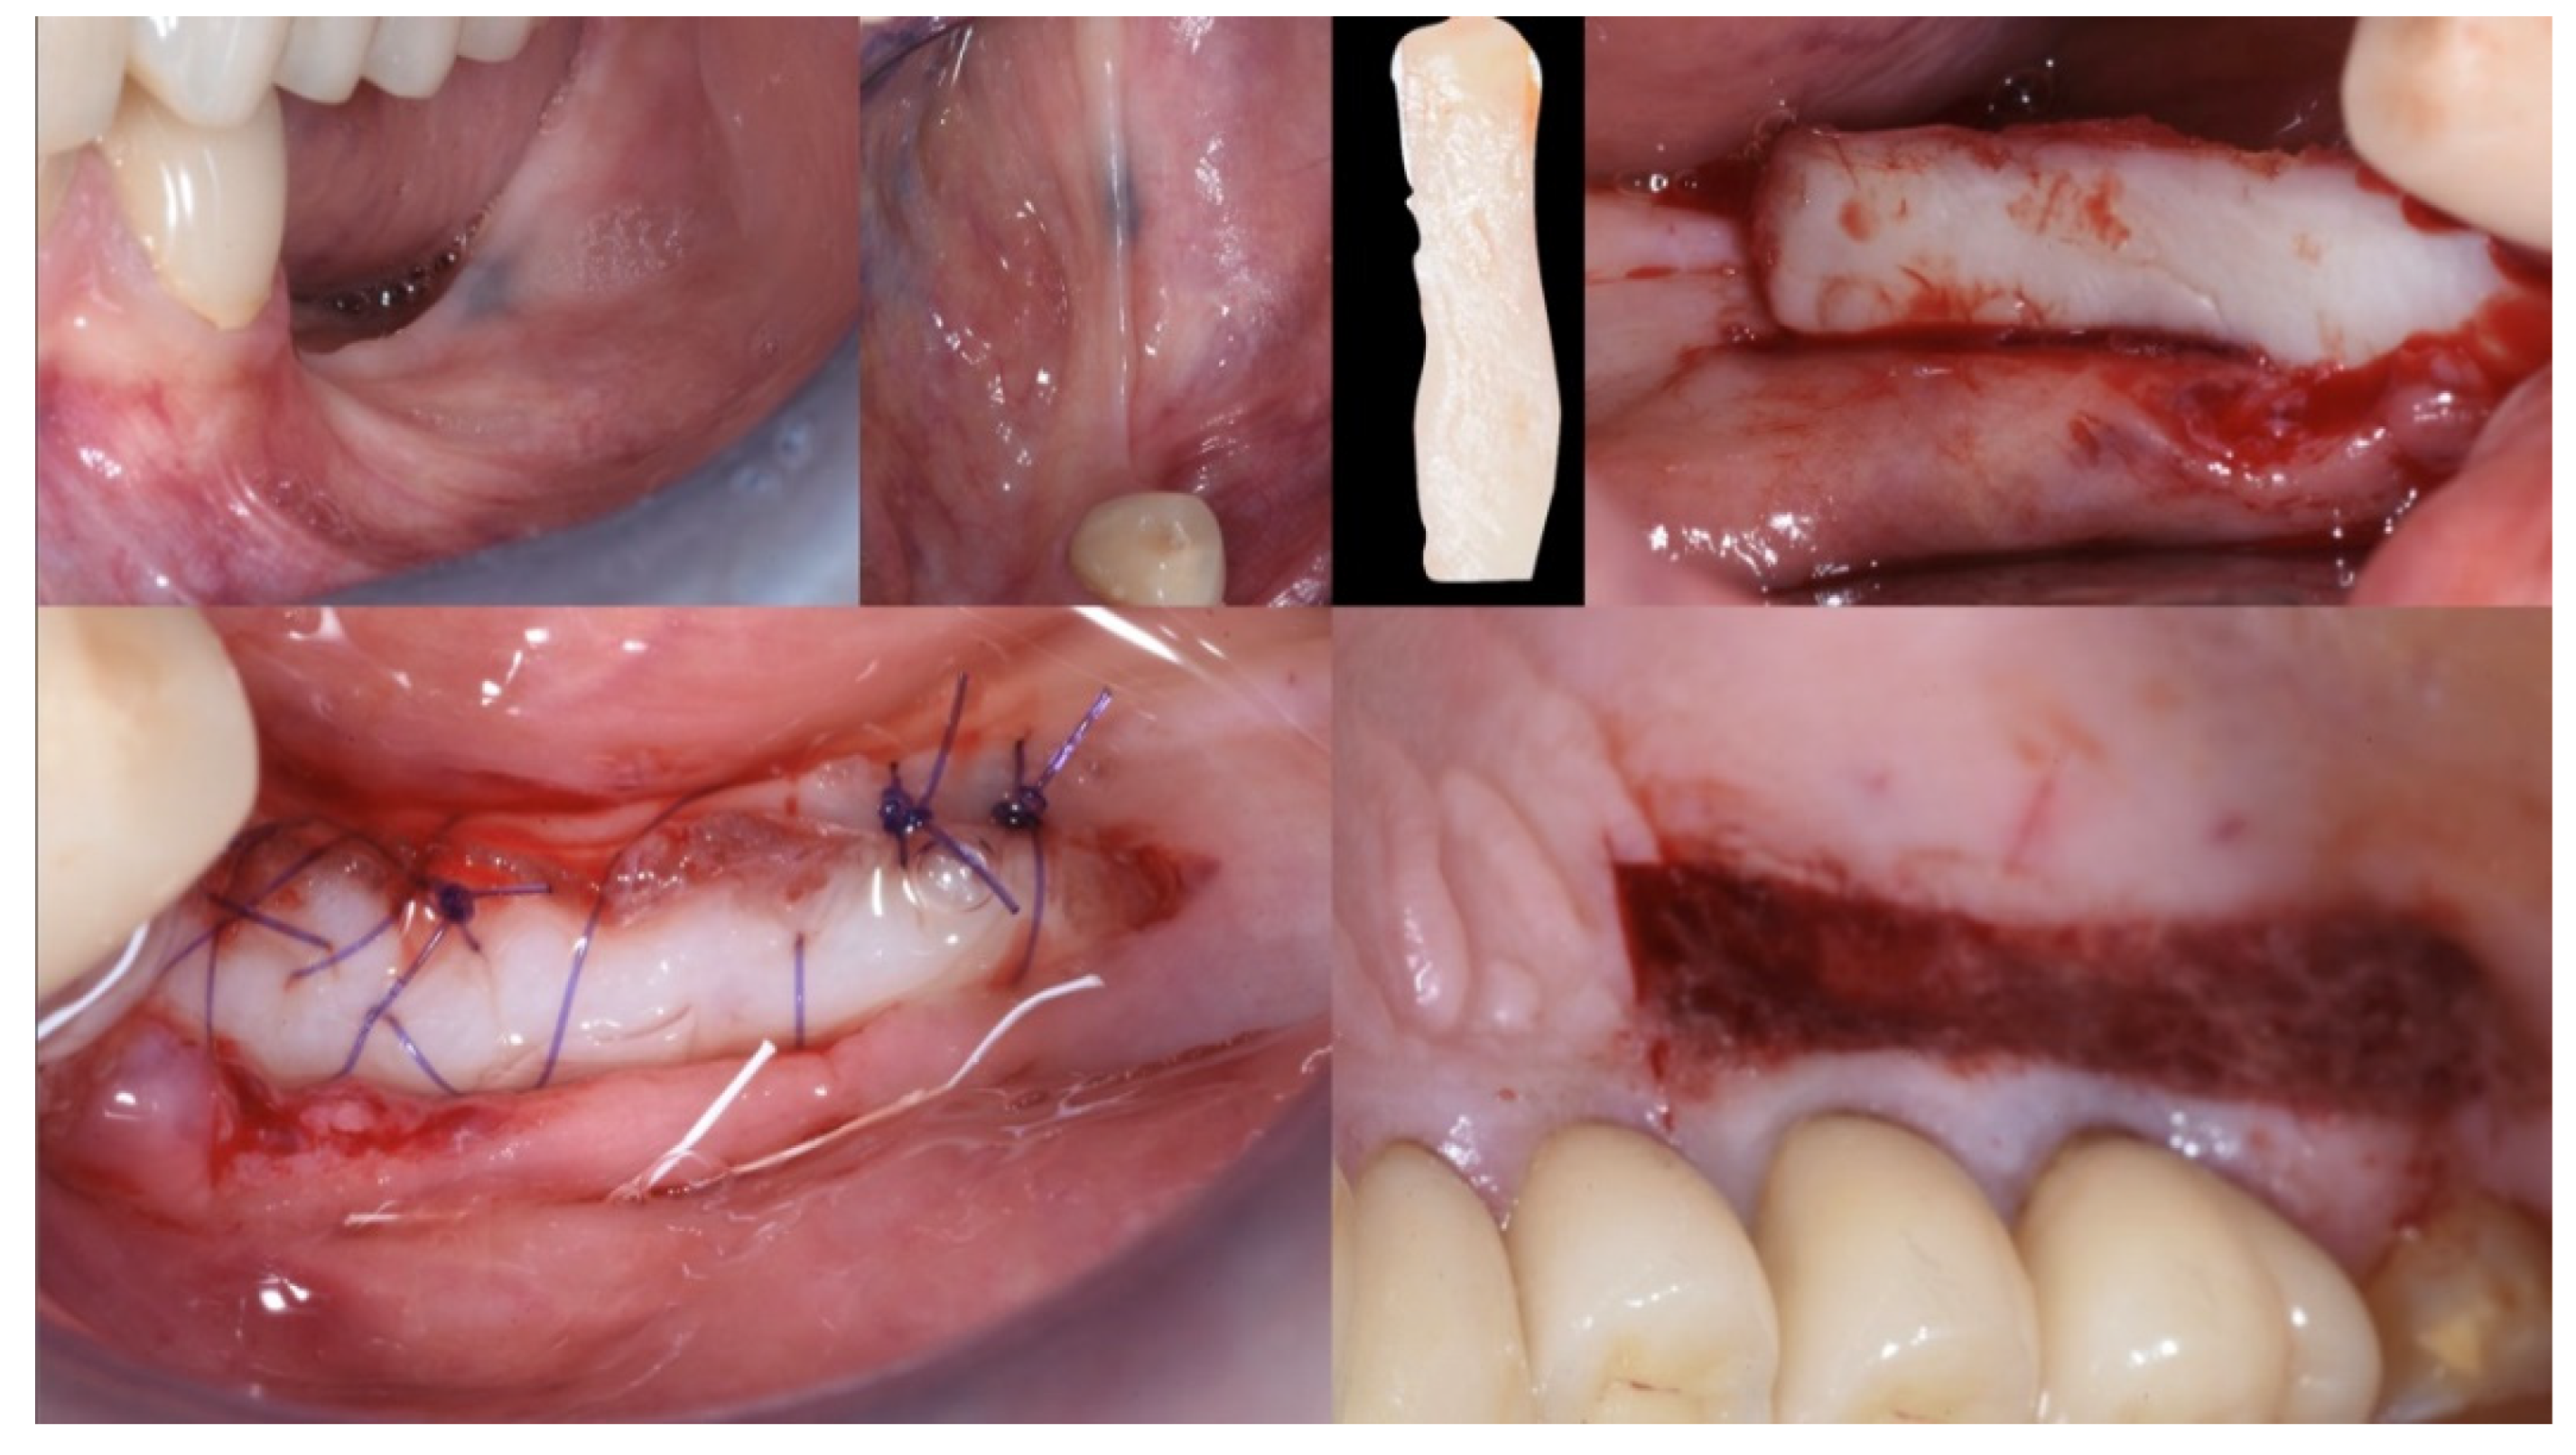

3.2. Soft Tissue Augmentation

| T1 | Mucogingival Surgery (0 months) | Free gingival graft |